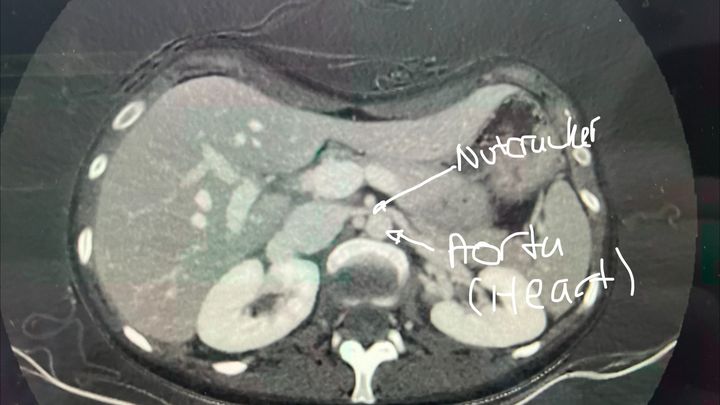

On March 4, 2026, my sister Margaret (MJ), a young adult, will undergo a groundbreaking procedure in London, Ontario. This complex, full-day surgery will be performed by a transplant team in London alongside a transplant surgeon flying in from Edmonton to treat severe left renal vein compression, known as Nutcracker Syndrome. In this condition, the vein responsible for draining blood from the left kidney becomes compressed between the aorta and the superior mesenteric artery (SMA), leading to impaired blood flow, increased venous pressure and compromised kidney function. This also causes an increase in blood pressure (144/108) and heart rate (up to 210bpm).

MJ is living with a rare and extraordinarily complex combination of four vascular compression disorders, which her team has unheard of all at once: Nutcracker Syndrome, a failed Median Arcuate Ligament Syndrome (MALS) surgery in 2023, Pelvic Congestion Syndrome, and May–Thurner Syndrome. These conditions have caused devastating effects on her health and quality of life, including over 30 pounds of unintentional weight loss and a critically low BMI.